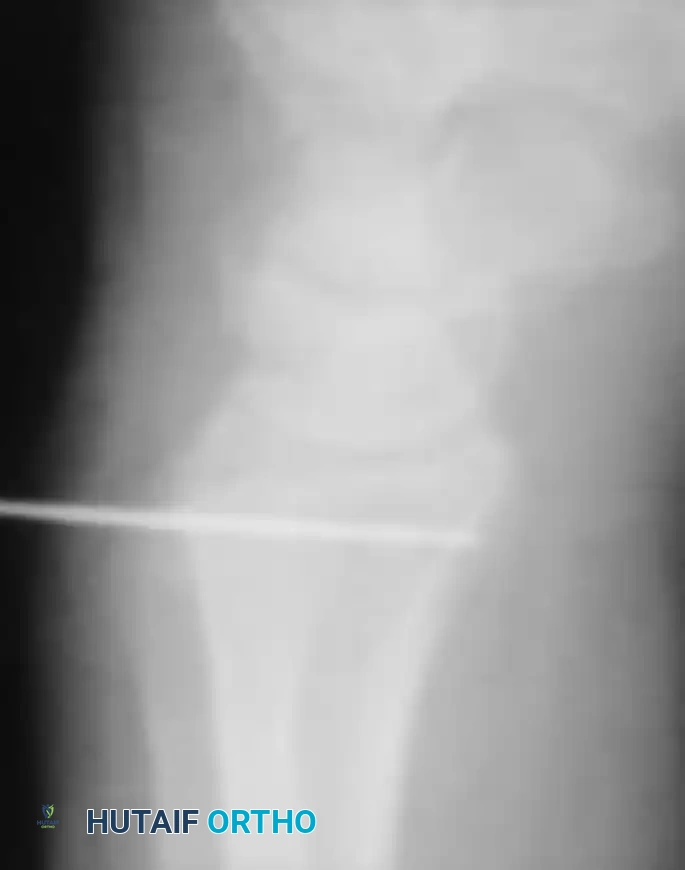

- Using C-arm fluoroscopy, drive a guidewire for a 2- to 4-mm cannulated drill through the radius from dorsal to palmar.

- Trajectory: The starting point must be far enough proximal to the lunate fossa and lateral (radial) to the articular surface of the sigmoid notch so that a 5-mm tunnel can be reamed without fracturing into the radiocarpal joint or the DRUJ.

- Use posteroanterior and lateral fluoroscopy to confirm that the guidewire is safely and accurately placed without passing completely through the palmar cortex prematurely.

- Use a cannulated 2- or 3-mm drill to create the initial pilot tunnel over the wire.

- Progressively enlarge the radial tunnel using noncannulated drill bits until it is sufficiently large (typically 4.5 to 5.0 mm) to allow smooth passage of the folded tendon graft.

- Placement: To avoid creating a stress riser and fracturing through the newly drilled ulnar tunnel, place the transfixion pin at least 2 cm proximal to the ulnar tunnel.

- Advance the pin through the ulna, across the interosseous space, and through the lateral (radial) cortex of the radius. Cut the point of the pin off beneath the skin on the radial side, and cut the trailing shaft beneath the skin on the medial (ulnar) side of the forearm.